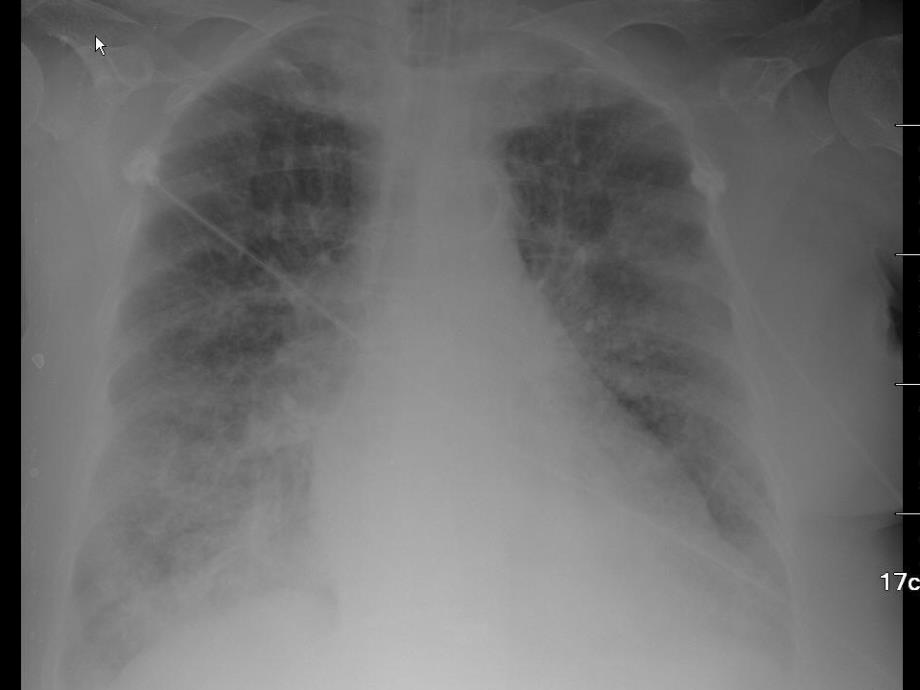

10、阻力Increased RawHigher PTA顺应性降低的原因顺应性降低的原因o 肺僵硬肺僵硬 水肿水肿 实变实变 纤维化纤维化 肺不张肺不张o 胸壁僵硬胸壁僵硬 脊柱侧弯或其他胸壁畸形脊柱侧弯或其他胸壁畸形 肥胖肥胖 腹水或腹胀腹水或腹胀o 肺受压肺受压 气胸气胸 胸腔积液胸腔积液o 动态肺充气动态肺充气反映肺顺应性反映肺顺应性-高压报警高压报警Lung Compliance Changes and the P-V LoopPreset PIPVT levelsCOMPLIANCEIncreasedNormalDecreasedPressure Targeted Ventilation压